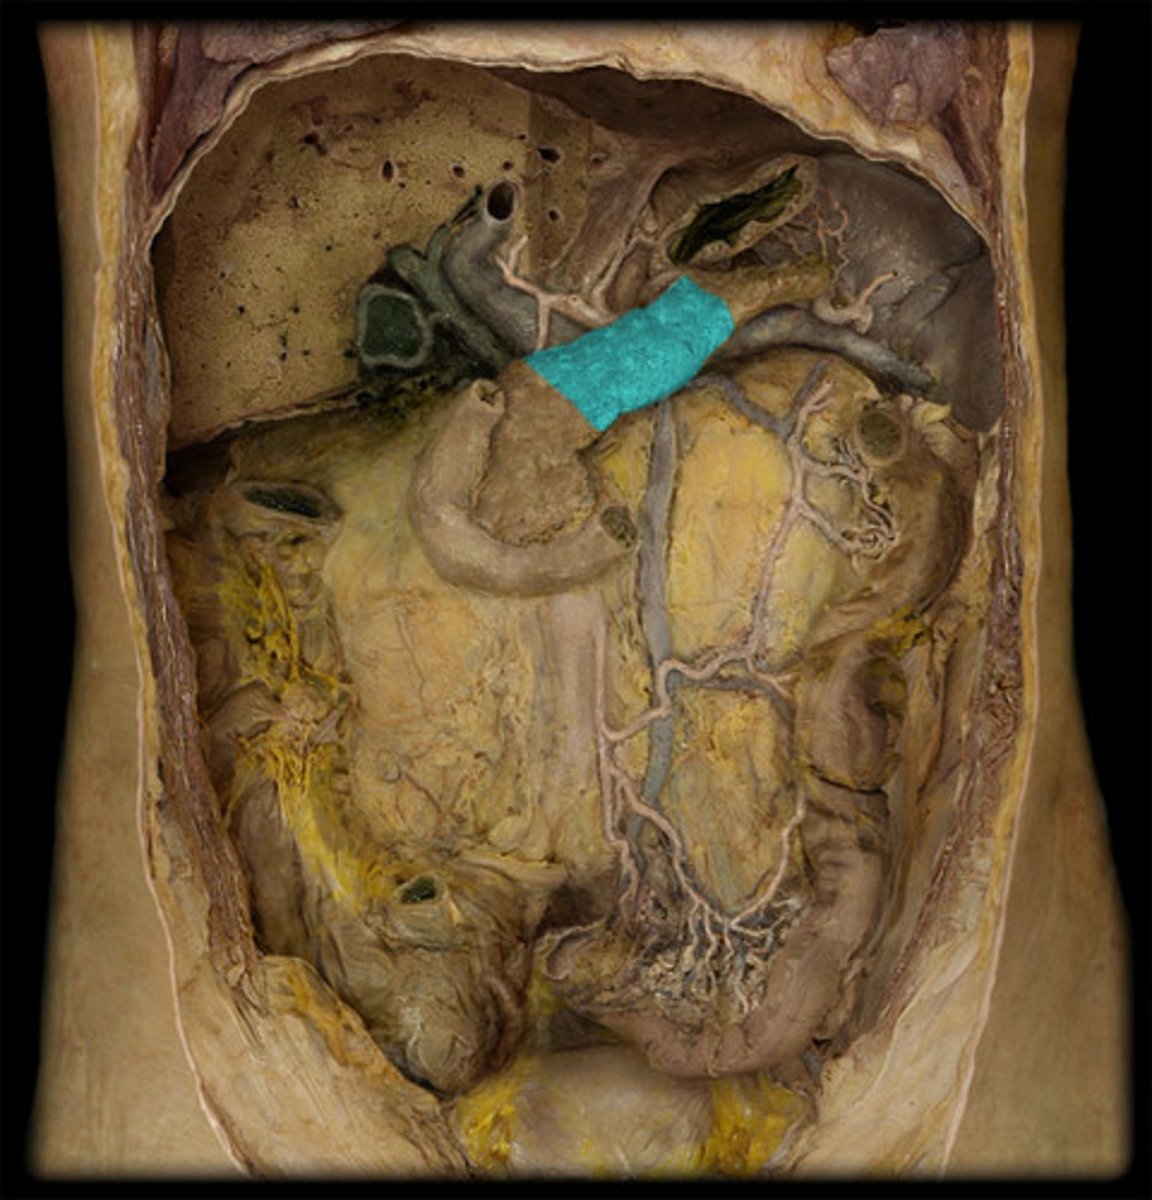

What is this?

Body of the pancreas

Tail of the pancreas

Pancreatic duct

The bile duct and pancreatic duct form the...

Hepatopancreatic ampulla

The hepatopancreatic ampulla drains into the...

Ampulla of Vater

Splenic artery

What are the splenic artery branches?

Short gastric arteries

Left gastroomental artery